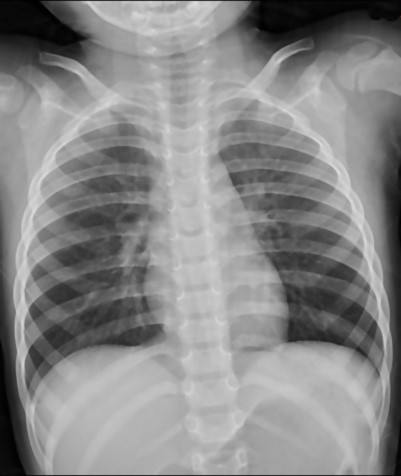

开云手机登录入口·(中国)官方网站的第八代设备MobileDaRt MX8进入中国市场也有段时间,以其优秀的移动性、便捷的操控性、高稳定性、图像清晰等特点得到国内用户的高度认可。特别是开云手机登录入口·(中国)官方网站的散射线抑制功能,把床旁摄影的图像质量提高到新的高度。该功能也就是现在常说的虚拟滤线栅,开云手机登录入口·(中国)官方网站散射线抑制使移动DR真正的进入到了无“栅”时代。

虚拟滤线栅

|

通过以上病例可以看出同一个病人,分别在不使用滤线栅,使用实体滤线栅,和使用虚拟滤线栅之后图像,可以看到右边两幅图像的对比度较左边图像明显提高。而且国内临床数据显示肥胖患者明显优于正常体型和偏瘦体型。